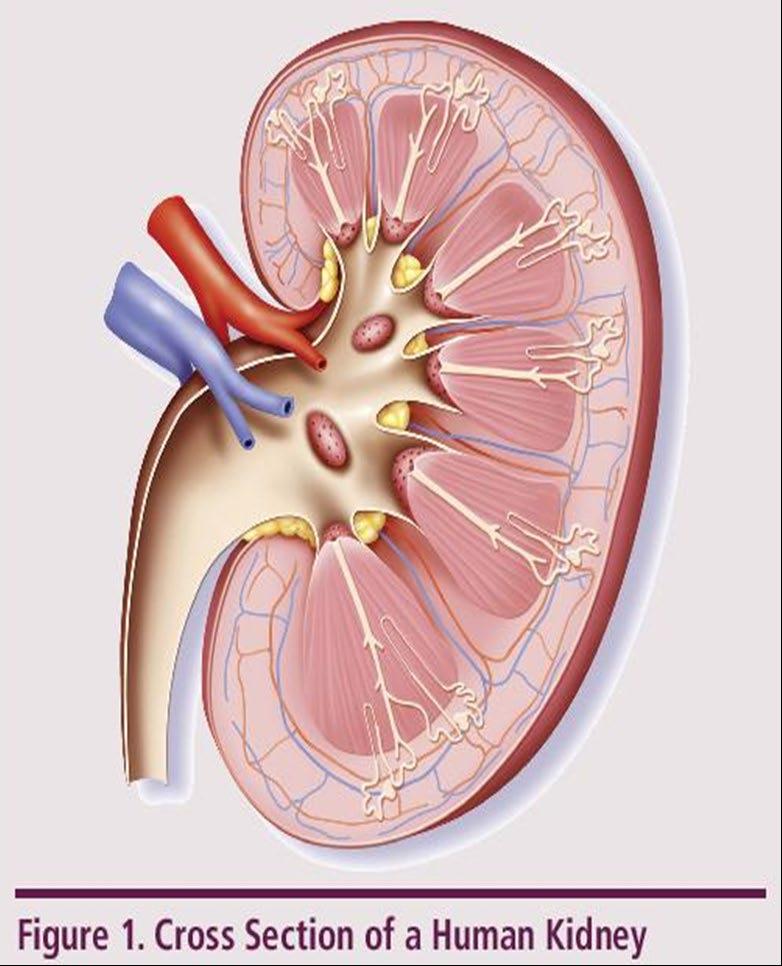

►Risk Factors – Active multiple myeloma (light chains, high calcium) – Other medical issues (ex: Diabetes, dehydration, infection) – Medications (MM treatment, antibiotics, contrast dye) ► Prevention – Drink, Drink, Drink – Avoid certain medications, when possible ► Treatment – Treatment for myeloma – Hydration – Dialysis Brigle K, et al. CJON. 2017;21(5)suppl:60 76. Faiman B, et al. CJON. 2017;21(5)suppl:19 36. Faiman B, et al. CJON. 2011;15suppl:66 76. Water glass: Cleanwateraction.org Many myeloma patients will experience kidney function problems at some point; it is important to protect your kidney function early and over time. 101

UNDERSTANDING CHANGES TO KIDNEY/RENAL FUNCTION